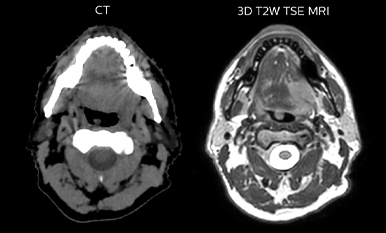

While CT clearly defines bone and cartilage, the modality’s limited soft tissue visualization makes head-and-neck structures often appear virtually indistinguishable from another. Coregistering an MRI dataset as a secondary information source for head-and-neck target and organ at risk (OAR) delineation is vital, according to La Tour’s Dr. Breuneval.

“MRI contributes substantially to visualizing head-and-neck lesions compared to CT and allows a better differentiation of normal from abnormal tissue,” he explains. “Tumor edges and extracapsular lymph node extension – as well as OARs, such as parotid glands, pharyngeal muscles and the brachial plexus – are better depicted. The resulting benefit is that tumor margins may be reduced and OARs better spared.”

Comparison of CT simulation scan (left) and T2W 3D MRI (right)